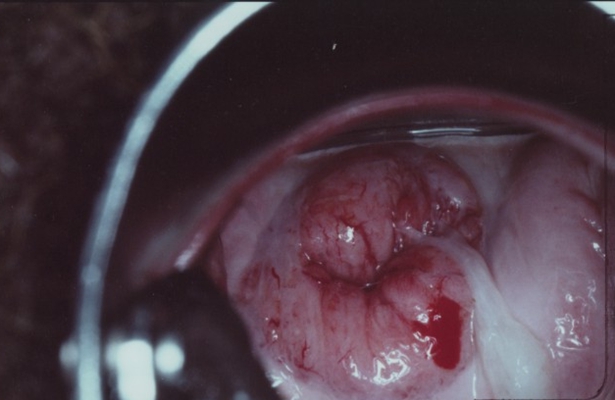

子宮頸癌前病變圖片

宮頸癌的早期症狀

宮頸癌的早期症狀

宮頸癌的早期症狀

宮頸癌的早期症狀

宮頸癌的早期症狀

宮頸癌的早期症狀

宮頸癌的早期症狀

宮頸癌的早期症狀

宮頸癌的早期症狀

宮頸癌的早期症狀